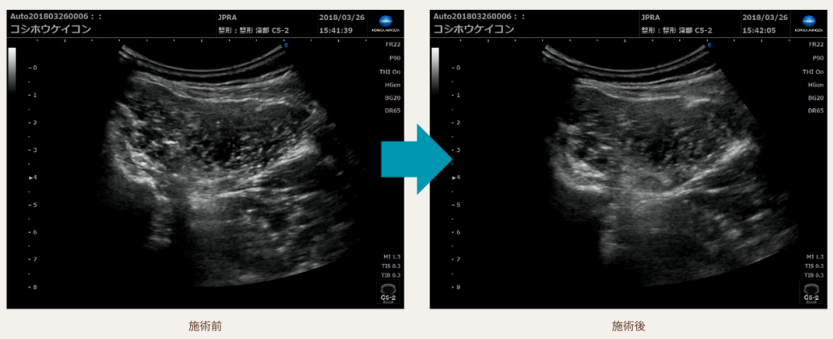

超音波エコーで証明された施術の変化

当院の施術による人体の変化を、超音波エコーを用いた科学的な方法で観察されました。

この進歩的な技術により、治療の効果が視覚的にも確認できるようになりました。

患者様は、この客観的な証拠に基づいた施術を受けることができます。

科学的な根拠に裏打ちされた当院のアプローチは、腰痛の改善に対して確かな信頼性を提供します。

科学的にも治療効果が認められています

「効率的に腰痛の改善を目指せる手技」

それを創り出すために、総額数億以上の研究費を費やし

手技の開発に没頭しました。

国立研究機関の協力のもと手技後の変化を可視化。

科学的にもその効果が立証されました。